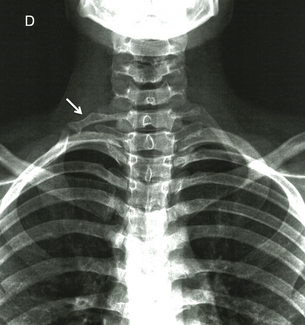

Pediatric thoracic outlet syndrome remains underrecognized. This case explores diagnosis and management considerations in a child with cervical rib compression.